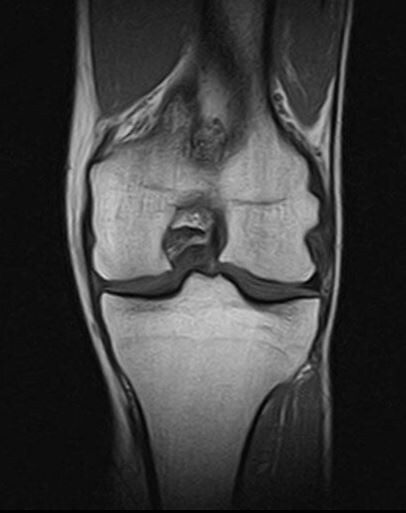

МРТ коленного сустава-когда нужно и зачем?

Коленный сустав-один из самых нагружаемых в нашем теле. Боль, хруст, отёк или ограничение подвижности-повод не терпеть, а разобраться в причине. Один из самых информативных методов-МРТ Что показывает МРТ?

Коленный сустав-один из самых нагружаемых в нашем теле. Боль, хруст, отёк или ограничение подвижности-повод не терпеть, а разобраться в причине. Один из самых информативных методов-МРТ

МРТ коленного сустава

Что показывает МРТ?

-повреждения менисков и связок (в т.ч. скрытые разрывы)

-воспаления и отёки тканей

-изменения в хрящах и костях

-наличие жидкости в суставе

-последствия травм